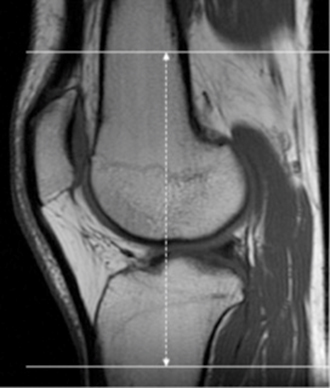

| SAG | PD (TE= 20msec) | TSE | 2.5-3 mm | 0.5mm | None | 15cm | Angle to lateral condyle |

| SAG | T2 SPAIR | TSE | 2.5-3 mm | 0.5mm | SPAIR | 15cm | Angle to lateral condyle |